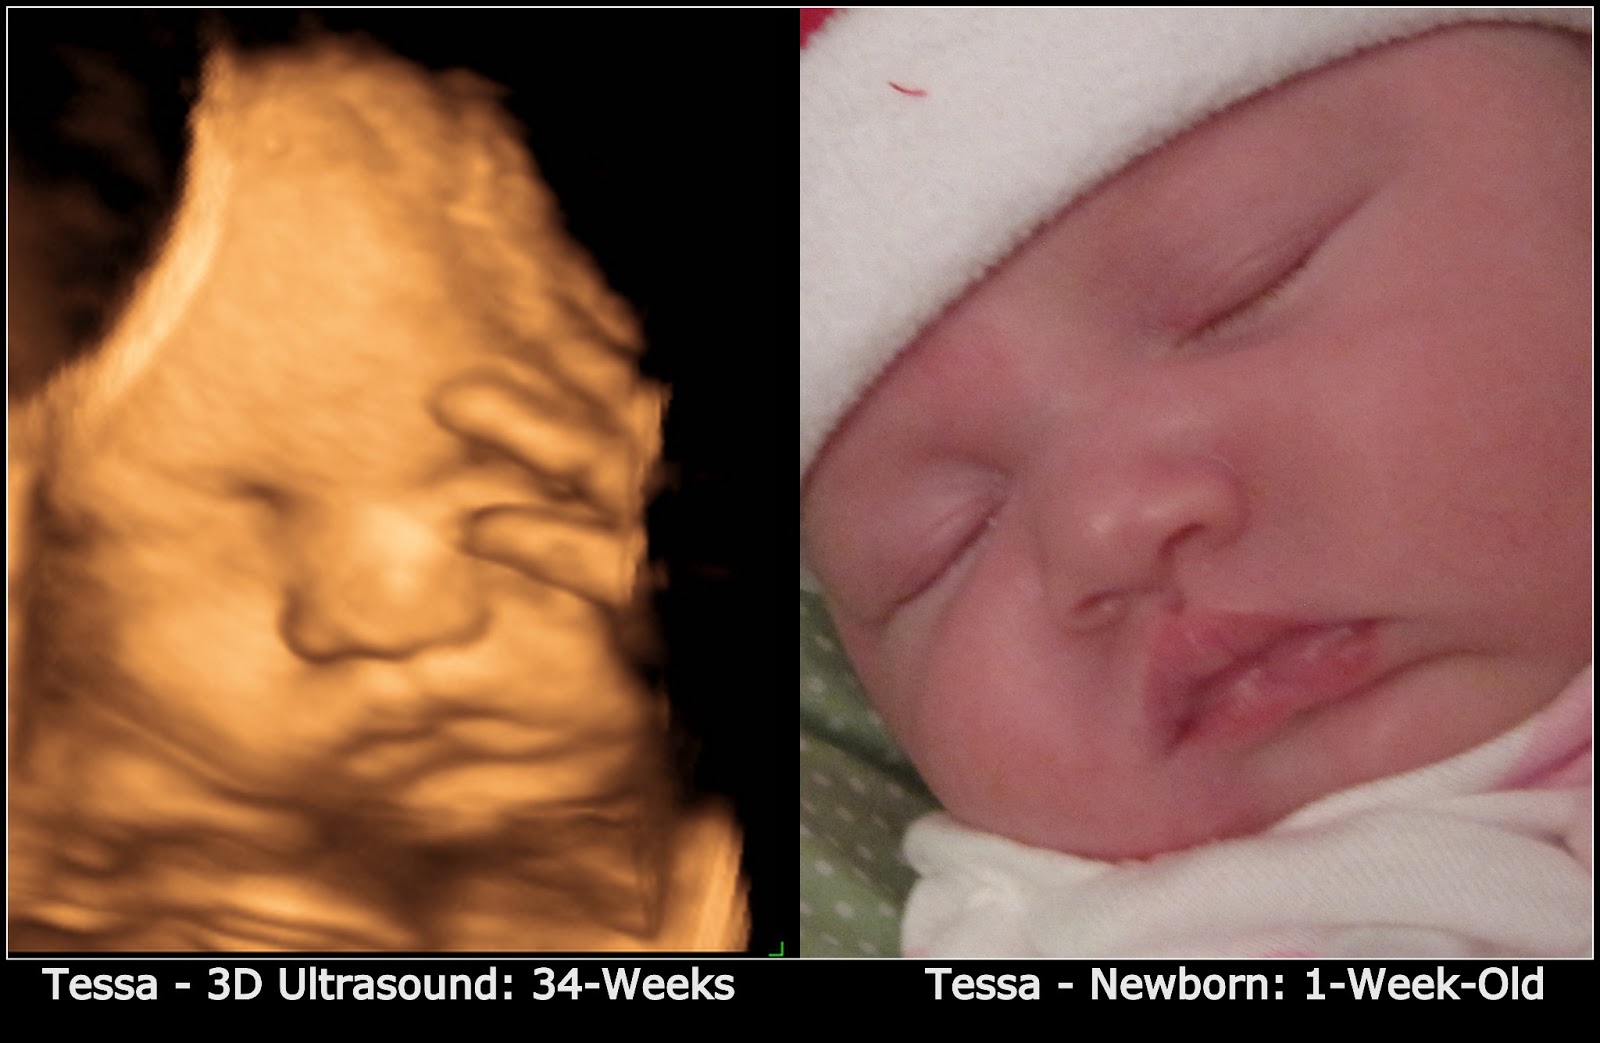

From www.mommysaidso.com

Mommy Said So 3D Ultrasound Photo SidebySide Comparison to My Actual Can A Baby Measure Bigger On An Ultrasound Toward the end of your third trimester, your health care provider or another member of your health care team might. The most accurate guesses for gestational age via ultrasound are from ultrasounds done sometime between the 8th. Later on in pregnancy, your baby is maxing out on the space available in your uterus, which makes his weight notoriously difficult to. Can A Baby Measure Bigger On An Ultrasound.